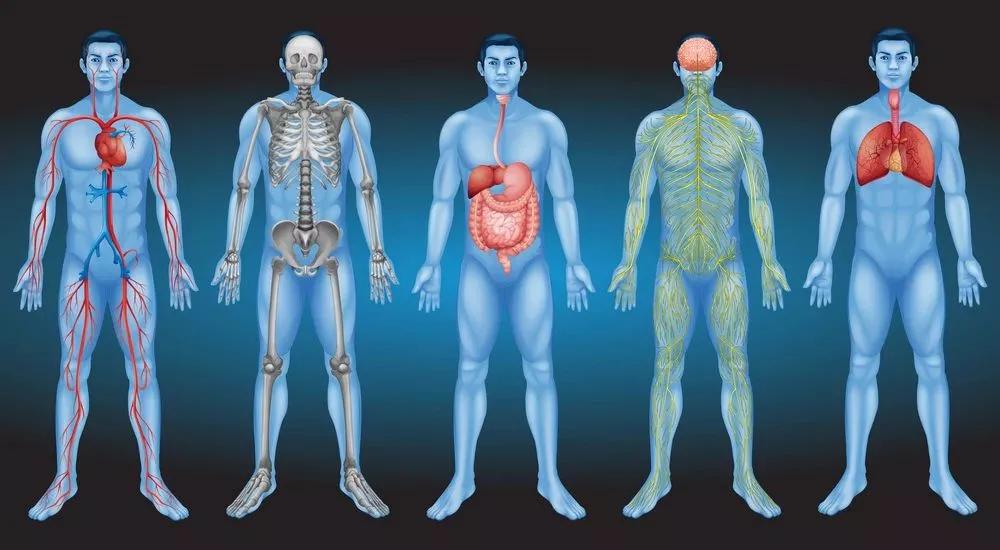

1、人体8大器官最不抗冻

寒潮来袭,羽绒服、围巾、帽子等御寒神器几乎人手必备。除了鼻子、耳朵、双手这些露在外面的部位,一些看不见的器官同样需要保暖。

01 血管:遇冷收缩易变脆

寒冷刺激造成心脏收缩力增强,周围血管收缩,导致收缩压及舒张压上升,易导致脑出血、脑梗塞等。

02 心脏:最怕温差大

室内外温差大,心脏负荷增加,严重时引发粥样硬化斑块破裂、血管堵塞,造成心绞痛或心肌梗死。

03 肺部:容易落下病根

冬季寒冷、干燥的空气,都要经过“肺”这个气体交换站进入体内。寒冷空气容易引起咳嗽、胸闷,甚至哮喘、呼吸困难等问题。

04 肠胃:代谢会变慢

06 关节:容易受伤

气温较低时,血管收缩,肌肉和韧带柔韧性较差,对关节的保护减弱,容易造成关节损伤及摔伤骨折。

07 耳朵:抗冻能力最差

08 前列腺:也会“感冒”